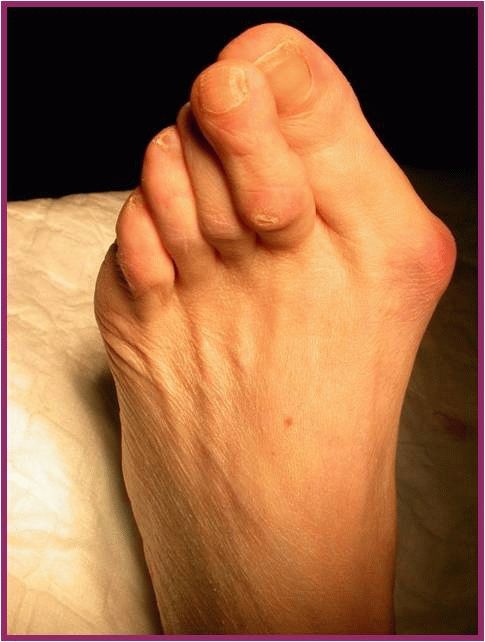

Симптомы и лечение остеоартроза узелков Гебердена: фотогалерея